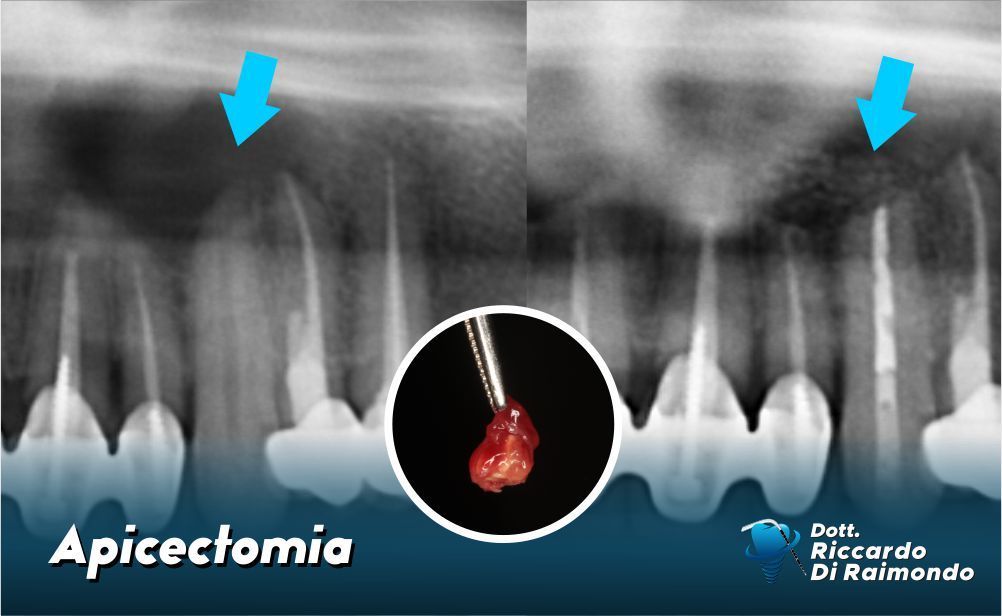

L’apicectomia è un intervento di microchirurgia che consiste nella rimozione dell’apice (cioè la punta) della radice del dente, insieme al tessuto infetto che lo circonda. Viene eseguita quando un’infezione periapicale persiste nonostante una corretta devitalizzazione o un ritrattamento canalare.

Lo scopo è eliminare il focolaio infettivo in modo mirato, senza dover ricorrere all’estrazione del dente. È una procedura conservativa, indicata quando si vuole salvare un dente compromesso ma ancora potenzialmente mantenibile.

L’apicectomia è spesso l’ultima possibilità per salvare un dente che, altrimenti, verrebbe estratto. Se eseguita in modo corretto e in assenza di controindicazioni, ha una percentuale di successo elevata e consente di evitare soluzioni più invasive come ponti o impianti.

Il Dott. Riccardo Di Raimondo esegue questo tipo di intervento con tecniche microchirurgiche avanzate, strumenti ad alta precisione e materiali biocompatibili di ultima generazione, con risultati predicibili e riducendo il post-operatorio al paziente.